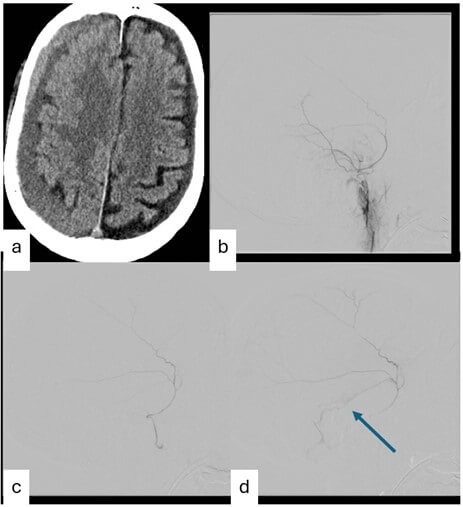

A total of 55 patients (43 male; mean age- 62.7 years; median age- 65 years) underwent EMMA at our institution during the study period. Table 1 summarizes the demographic, clinical, and angiographic characteristics of the cohort. Of these, 41 underwent surgical intervention prior to EMMA, while 14 did not. One patient who underwent surgery after embolization was included in the non-surgical group for analysis. Bilateral CSDH was observed in 15 patients, all of whom were male. A total of 64 middle meningeal angiograms were performed. Three patients did not undergo embolization due to difficulties accessing the MMA, MMA origin from ophthalmic artery, and MMA ligation during surgery. Arteriovenous Fistula (Figure 1). Eighteen patients (32.7%) were found to have AVFs. Because some patients underwent bilateral EMMA, a total of 64 embolizations were analyzed. AVFs were detected in 21 angiograms (32.8%). Four patients had more than one AVF (Table 1).

The most common arterial supply was from the posterior division of the MMA (18/26, 69.2%) and the most common venous drainage was into the osteodural veins (18/26, 69.2%). No residual AVFs were observed on post-embolization control angiograms. No patient experienced recurrence of cSDH during the follow-up period. Table 2 presents various demographic and clinical factors associated with AVFs. Prior surgical drainage was associated with lower prevalence of AVFs (32% vs 53%, p=0.028). Inter-rater agreement was moderate (k= 0.42). In five patients, the AVFs were deemed iatrogenic and excluded from the analysis.

Our study demonstrates that the non-iatrogenic AVFs are present in approximately one-third of patients with cSDH undergoing EMMA, with multiple AVFs observed in 6.25% of patients. Prior surgical drainage was associated with a lower prevalence of AVFs. Most AVFs were supplied by posterior division of MMA and drained into osteo-dural veins. Prior literature has reported AVFs in association with cSDH primarily through isolated case reports and small series, limiting accurate estimation of prevalence [12, 14, 15]. Proposed mechanisms included congenital dural shunts becoming patent after hemodynamic changes or angiogenesis following craniotomy. However, these mechanisms alone do not fully explain our findings, as AVFs were present in only one-third of patients and were less prevalent in those who had undergone surgery.

Importantly, AVFs in our cohort were often visible only on microcatheter angiography, supporting the hypothesis that these may represent physiological dural shunts (< 12 μm) not visible on global DSA [12, 14, 16]. This observation suggests that such shunts may be underrecognized during routine angiography. Although procedural iatrogenesis remains a concern, cases suspicious for iatrogenic AVFs were systematically excluded, strengthening the validity of our prevalence estimate. Consistent with prior case reports, no patient experienced cSDH recurrence following embolization, even in the presence of AVFs [12, 18]. Given the potential role of both MMA flow and dural AVFs in sustaining cSDH, systematic evaluation for AVFs during EMMA is warranted. When AVFs are identified, liquid embolic agents may be preferable, as they allow effective fistula occlusion without venous migration.